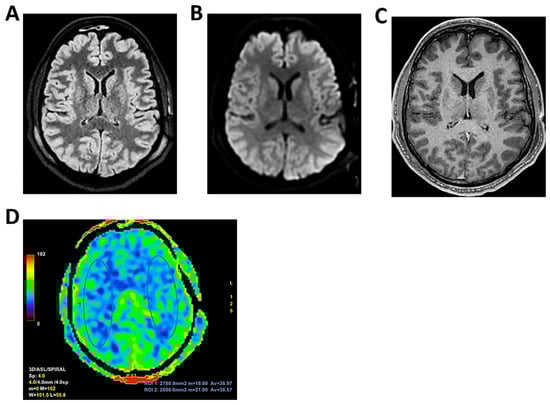

Figure 9.

MRI of patient 4 group 2. A 35-year-old HIV-positive man, diagnosed in 2018 with pneumocystosis (PCP) and non-compliant with Highly Active AntiRetroviral Therapy (Biktarvy), presented with bilateral otalgia, progressive hearing loss, left-sided hemiparesis, and impaired coordination. He was hospitalized and reinitiated Biktarvy and PCP prophylaxis with Bactrim. He received broad-spectrum antibiotics for bilateral otomastoiditis and ganciclovir for CMV viremia. Brain MRI revealed findings consistent with progressive multifocal leukoencephalopathy (PML). After discharge, worsening left hemiparesis and new-onset dysarthria led to readmission. A follow-up CT showed progression of subcortical white matter lesions. Lumbar puncture, urine, and plasma were all positive for JC virus. The patient was transferred to the ICU for further management. On day 2, TCCD showed PI of 1.50 on the right and 1.07 on the left, indicating mild asymmetry but no definitive signs of intracranial hypertension. (A) MRI exam shows large areas of altered signal intensity, without significant mass effect, hyperintense in 3D axial FLAIR sequence, (B) with peripherical diffusion restriction in axial DWI sequence, (C) without contrast enhancement in 3D axial T1 FSPGR, involving both cortical and deep regions of the frontal, temporal and parietal regions bilaterally, as well as right insular and thalamic regions. Additionally, the brainstem with left-sided predominance and the right middle cerebellar peduncle are involved. These alterations are consistent with PML. (D) MRI perfusion study documents minimal increase in CBF in the more cranial regions on the right. Blue circles indicate the ROI used for quantitative CBF analysis.

Figure 10.

MRI of patient 5 group 2. A 67-year-old woman with schizophrenia presented to the ER with lethargy and vomiting, following 10 days of fever and dry cough treated ineffectively with Medrol and Cefditoren. Brain CT showed a left temporoparietal hypodensity (sequela) and supratentorial ventricular dilation without midline shift. The lumbar puncture was positive for Listeria monocytogenes (FilmArray). Due to neurological deterioration (GCS 7), she was transferred to the ICU. On day 2, TCCD showed PI values of 1.65 (right) and 1.89 (left), indicating increased cerebral vascular resistance without clear signs of intracranial hypertension. (A) 3D axial FLAIR shows marked and diffuse atrophy of the brain tissue, more pronounced in the left hemisphere where some areas of enlargement of the cerebrospinal fluid spaces are observed, more prominent in the parietal region, and diffuse dilation of the supraventricular system, particularly in the occipital horns. (B) Perfusion study reveals minimal asymmetry in cerebral perfusion values sampled at the level of the semioval centers. Blue circles indicate the ROI used for quantitative CBF analysis.

The remaining two patients in this group experienced poor outcomes. One was diagnosed with progressive multifocal leukoencephalopathy (PML) due to JC virus and presented with a right-dominant perfusion asymmetry and elevated right-sided PI (1.50). MRI revealed extensive subcortical and infratentorial lesions, including the brainstem (Table 3 and Figure 9).

The second patient, affected by L. monocytogenes meningoencephalitis, showed bilateral elevation of PI (1.65 and 1.89) and significant CBF asymmetry (right CBF: 105 mL/100 g; left CBF: 91 mL/100 g) (Table 3 and Figure 10).

Both patients died by day 28. Notably, these two cases demonstrated a mismatch between regional perfusion and vascular impedance, consistent with cerebrovascular dysregulation and loss of autoregulation.